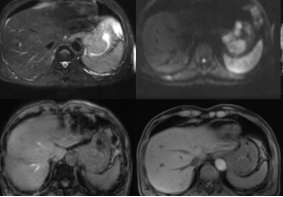

MRI的工作原理跟CT可不太一样。它不用X射线,而是用一个超级强大的磁场和无线电波来“激活”你身体里的氢原子。这些被“激活”的氢原子会发出微弱的信号,MRI机器就像是个超级灵敏的“收音机”,能捕捉到这些信号并把它们转换成详细的身体内部图片。它不仅能提供横截面图像,还能生成三维图像。这样一来,医生就能看到比CT更加细腻的身体结构了。无论是大脑、脊髓,还是关节和软组织,MRI都能提供清晰的视图,成为现代医学中不可或缺的诊断工具。

(二)MRI能看出胃癌啥?

MRI在胃癌诊断上也是个高手。它不仅能看出肿瘤的位置、大小和形状,还能显示出肿瘤内部的血流情况。这对于判断肿瘤的良恶性可是非常有帮助的。更重要的是,MRI还能帮助医生评估手术的可行性。比如,要是肿瘤已经长到了血管或者神经旁边,手术风险可就大了。这时候,MRI就能给医生提供一个更加准确的“作战地图”,让他们能更好地制定手术计划。